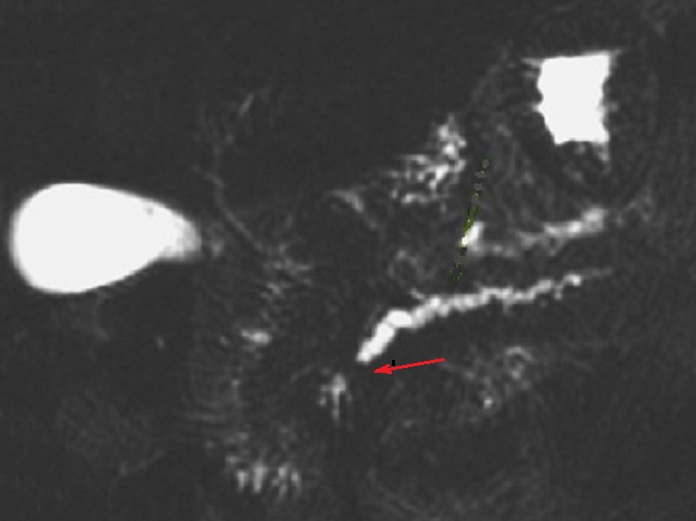

Image radiologique Wirsungo-

cholangio IRM ( Bili -IRM ) d'une adenocarcinoma de

la tete du pancreas en presence comme une ostacle de

la conduit de CPP ( canal pancreatique principale ) . Le canal

principal du pancreas en amont est dilate et voie

biliaire principale est encore en vue legerement

distendue |

Une autre cas de tumeur

cephalique du pancreas . Le canal pancreatique

principale en amont est dilate marque ( fleche rouge ) .

Image radiologique Wirsungo - cholangio IRM . |